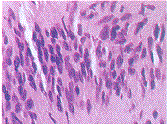

图3 例1.栅栏样排列的梭形细胞束形成条带,胞浆嗜酸性(H-E染色,放大倍数×64)

图4 例1.核卵圆形,胞浆内有空泡(H-E染色,放大倍数×82)

图5 例2.细胞核排列成平行条索样,构成Antoni a-条纹型(H-E染色,放大倍数×160)

图6 例2.未见良性梭形细胞或小而色淡的核仁(H-E染色,放大倍数×204)